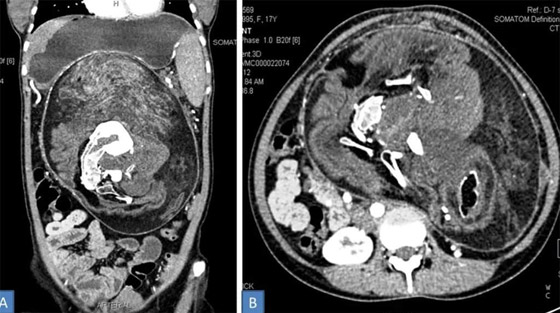

4- جنين داخل جنين:

أحيانًا يستطيع توأم مغاير خارجي التواجد بشكل كامل داخل توأمه الذي يكون سليمًا، وهو ما يعرف باسم "الجنين داخل الجنين" أو Fetus in Fetu. هي ظاهرة نادرة للغاية، حيث لم يتم توثيق أكثر من 200 حالة عبر التاريخ، وعادة ما يكون هنالك جنين واحد داخل الجنين، لكن في إحدى الحالات وجد الأطباء 11 جنينًا داخل جنين.

إنها ظاهرة طاف حولها جدل كبير بين الباحثين والعلماء حول الطريقة التي تحدث بها، كما أن بعضهم لا يتفق حتى على أن "الجنين" الداخلي يعتبر توأمًا أساسًا، حيث يعتقد هؤلاء أن ظاهرة "الجنين داخل الجنين" ما هي إلا حالة ورم مسخي متطور، الذي هو عبارة عن ورم يتكون من عدة أنواع من أنسجة الجسم.

كما يوجد فريق آخر من الباحثين الذين يعتقدون بأن الظاهرة تحدث بسبب وقوع خلل أثناء تطور الجنين، حيث تنقسم بعض الخلايا الجذعية التي من المفترض أن تتطور لتصبح أعضاءً أخرى بشكل غريب. لكن آخرين يقولون بأنه توأم حقيقي، ذلك أن الجنين داخل الجنين يملك عمودا فقريًا، وغالبا ما تتطور لديه أعضاء مثل أطراف الجسم.

بالطبع قد يكون أي من الآراء والنظريات السابقة صحيحًا، حيث قد تكون هنالك الكثير من الطرائق المختلفة التي تنتهي بجنين متطور بشكل جزئي داخل جنين آخر متطور بشكل كامل. قد يعني هذا أن دراسة هذا النوع من التوائم قد يساعد الأطباء على فهم كيف أن بعض الأورام الجنينية تصبح مصدر إشكال بينما تبقى أورام أخرى حميدة، كما قد تساعدنا على فهم بعض الأمور المثيرة حول البرمجة التطورية للخلايا.

قد يكون حدوث ظاهرة الجنين داخل جنين راجعًا لكون أحد الجنينين يحتوي الآخر في مرحلة ما من تطورهما، أي أن الظاهرة أقرب إلى فكرة الالتحام لكنها أكثر تطرفًا. وهو ما لا يعتبر بعيد المنال مثلما قد يبدو عليه، لأنه توجد حالات موثقة لأجنة توأم يمتص أحدها جزءا من الآخر أو يمتصه ويحتويه بشكل كامل.